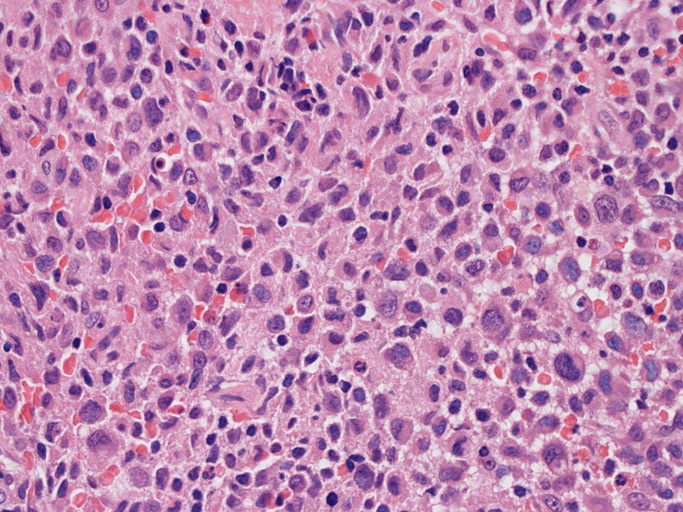

大型細胞の増殖よりなる腫瘍。縦溝,しわ,切れ込みのある核をもった大型細胞も出現する。クロマチンは顆粒状で核小体も明瞭である。核分裂は >50/10hpfと多い。eosinophilsは少ない。壊死が多発することがある。未分化ないし低分化な細胞像, 組織所見のため鑑別診断は多岐にわたり、的確な免疫染色を行う必要がある。

皮膚に異型細胞の浸潤がみられる。異型細胞は表皮内に浸潤するほか、表皮真皮境界部, 真皮, 皮下脂肪組織にもびまん, 結節様の浸潤所見を示す。血管周囲に浸潤、集蔟する所見も多く見られる。 増殖浸潤細胞の核には類円形や腎臓形, またはへこみ, 切れ込み, 溝などを有する多型な核が認められる。クロマチンは粗でvesicularな核が多い。核小体の明らかな核もある。好エオジン性の核内封入体様構造も少数に見られた。mitosisは容易に認められる。hyperchromaticな多型核, bizzarreな細胞が高頻度に認められ異型度は高いと考えられる。細胞質は境界不明瞭, 淡明または泡沫様の 好エオジン性胞体である。